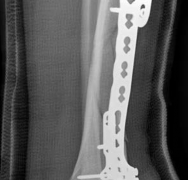

With the articular surface reconstituted, the surgeon's focus shifts to bridging the complex metaphyseal-diaphyseal dissociation. A pre-contoured anatomical locking plate is slid submuscularly or subcutaneously along the diaphysis using a MIPPO technique. The plate is positioned on the anterolateral or medial surface, depending on the preoperative plan and soft tissue constraints.

The distal portion of the plate is secured to the reconstructed articular block. It is imperative that the distal locking screws are placed parallel to the joint space, forming a rigid subchondral raft that supports the articular cartilage. Fluoroscopy is utilized extensively to ensure no screws have penetrated the joint. Once the distal block is secured to the plate, the diaphyseal segment is aligned. Length, alignment, and rotation are restored using manual traction or the femoral distractor. The proximal portion of the plate is then secured to the diaphysis using a combination of non-locking screws (to pull the bone to the plate) and locking screws (to create a fixed-angle construct). The working length of the plate is maximized by leaving several screw holes empty over the zone of comminution, promoting secondary bone healing.